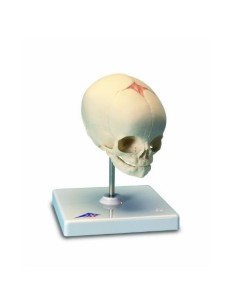

Dal cranio in 22 parti con incastri magnetici ai modelli di colonna vertebrale, da quelli di articolazioni a quelli di cuore, ogni pezzo della nostra collezione è progettato per un’immersione totale nello studio dell’anatomia umana. I nostri modelli, realizzati tramite scansioni di ossa vere, garantiscono un’esperienza tattile autentica e una fedeltà di peso quasi identica agli originali.

Essenziali per studenti e professionisti, i nostri modelli anatomici sono strumenti didattici che permettono di osservare le strutture anatomiche con precisione, eliminando la necessità di dissezioni o studi invasivi. Sono inoltre utili per spiegare ai pazienti le patologie, rendendo la comunicazione più efficace e risparmiando tempo prezioso.